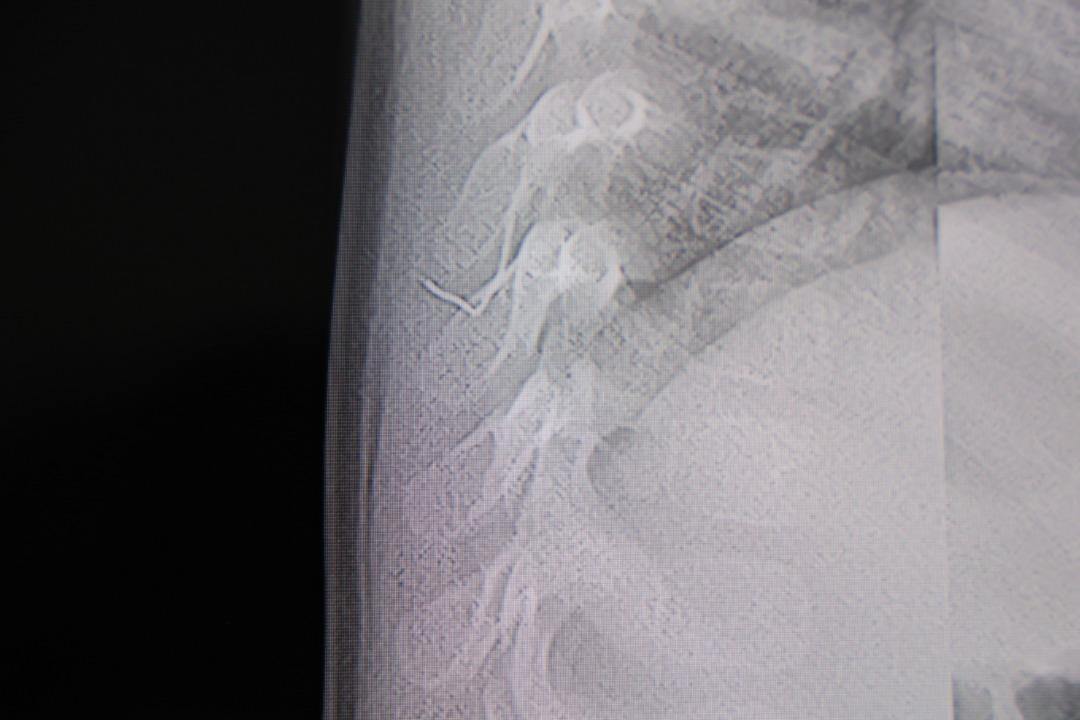

Yapılan tetkiklerde, yabancı cismin cilt altında, omurilik kanalına yakın bir bölgede olduğu ve akciğer zarına doğru ilerlediği belirlendi.

Çıkarılan cismin, ince zımba teline benzer metal bir tel olduğu ve yaklaşık 2 santimetre uzunluğunda bulunduğu tespit edildi. Hasta, aynı gün taburcu edildi.

Konuya ilişkin açıklama yapan Prof. Dr. İdris Altun, "Sırtında yabancı bir cisim olduğu söylenmiş ancak çıkarılamayacağı ve 8 yaşına kadar beklenmesi gerektiği ifade edilmişti. Bize başvurduğunda yaptığımız tetkiklerde, cilt altında, omurilik kanalına çok yakın ve akciğer zarına doğru ilerleyen bir yabancı cisim tespit ettik. Hastamızı tamamen uyutmadan, lokal anestezi ve sedasyon eşliğinde müdahale ederek lezyonu tamamen çıkardık. Çıkardığımız cismin ince zımba teline benzer, yaklaşık 2 santimetre uzunluğunda metal bir tel olduğunu gördük. Bu yabancı cisim alınmasaydı, bölgede enfeksiyon gelişebilirdi. Enfeksiyon sonucu omurilik kanalında ciddi hasarlar oluşabilir, çocuk büyüdükçe cismin hareket etmesine bağlı olarak omurilikte zedelenmeler meydana gelebilirdi. Ayrıca yana doğru ilerleyerek akciğer zarına ve akciğere batma riski vardı. Bu da enfeksiyona ve ilerleyen süreçte tümörle karışabilecek tablolara neden olabilirdi. Şu an hastamız gayet sağlıklı. Gerekli kontrolleri yaptık ve aynı gün taburcu ettik" dedi.